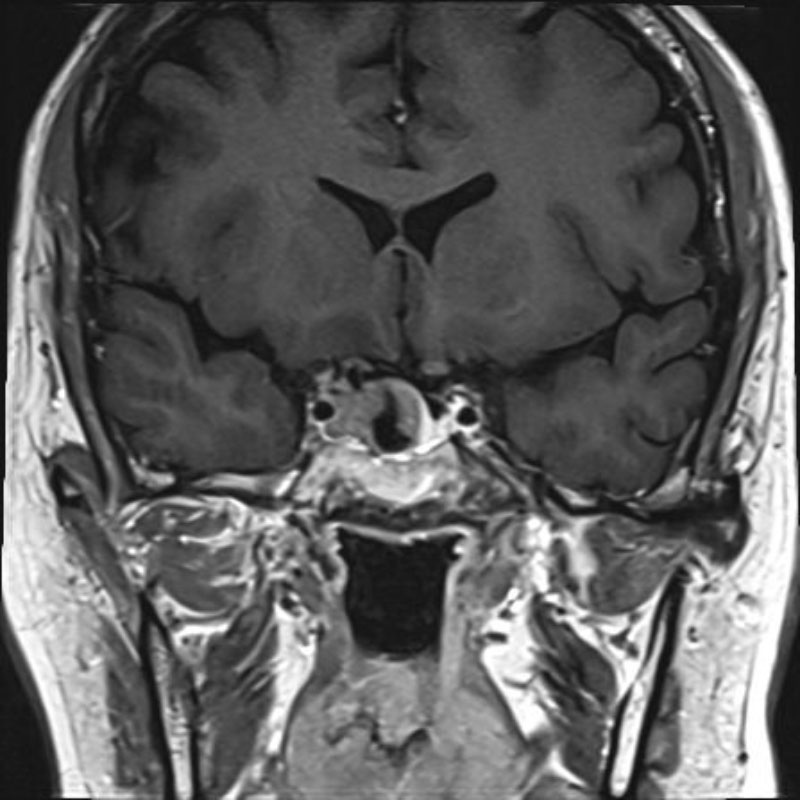

640

'25年6月

80代

傍矢状洞髄膜腫

頭蓋内腫瘍摘出術

No.’25_42 手術前1

No.’25_42 手術前2

No.’25_42 摘出 前

No.’25_42  摘出 中

No.’25_42 摘出 後